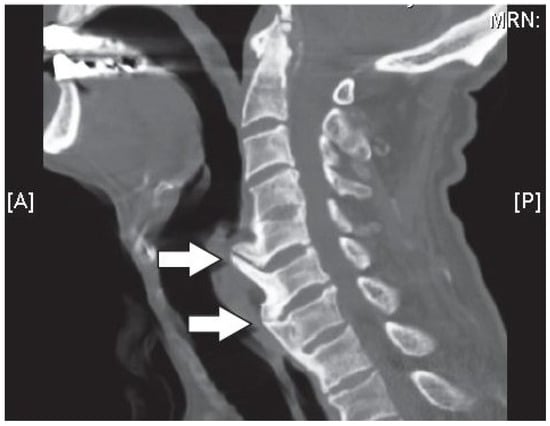

- Horkoff, M.; Maloon, S. Dysphagia secondary to esophageal compression by cervical osteophytes: A case report. BCMJ 2014, 56, 442–444. [Google Scholar]